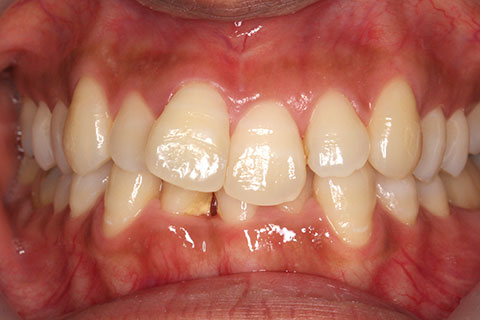

ハーフリンガル矯正3:上の歯のみ舌側矯正で治療(矯正期間24ヶ月)

治療中(開始直後)

- 年齢・性別

- 25歳女性

- 治療期間

- 2年0ヶ月

- 抜歯

- 上下4番抜歯

- 治療費

- 110万円

- 治療内容

- 施術の副作用(リスク)

- 表側矯正と比較して、力学的な操作性が複雑なため、ボーイングエフェクトを起こしやすい。